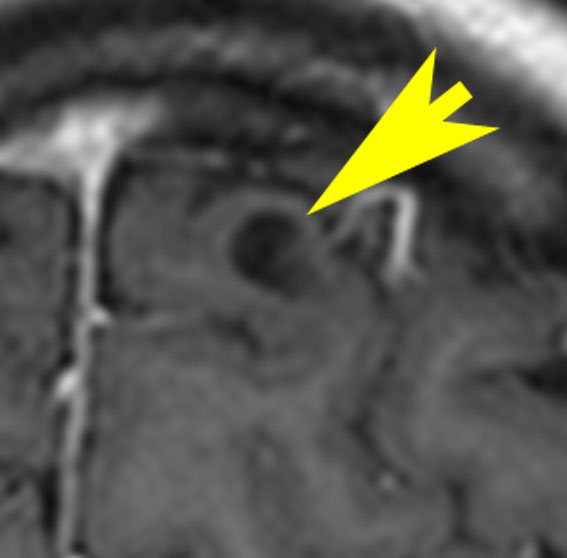

NF-2で脳腫瘍と間違っていはいけない大脳の病変

- MRIでグリオーマのようにみえますがそうではありません。T2強調画像で白く見えてガドリニウム造影されないのが一般的な特徴です

- 微小過誤腫 (microhamartoma)とか皮質異形成 (cortical dysplasia)とか血管周囲腔拡大 (Virchow-Robin space enlargement)とかいわれるものです

病理はとれないので確定できませんが,おそらく微小過誤腫 microhamartomaなのでしょう